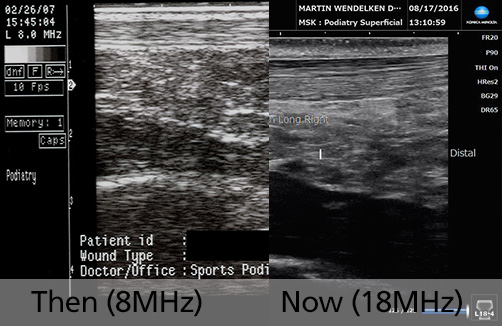

Then (2007) & Now (2020)

8MHz vs 18MHz